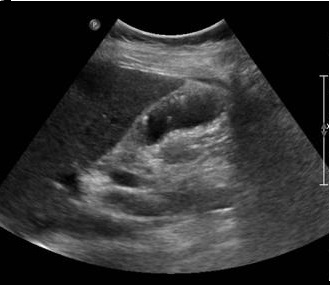

Image echographique en coupe

longitudinale de la vesicule biliaire : Aspect de

multiple formation polypoide adenomateuse

isoechogene de type pedicule ( fleche rouge ) . |